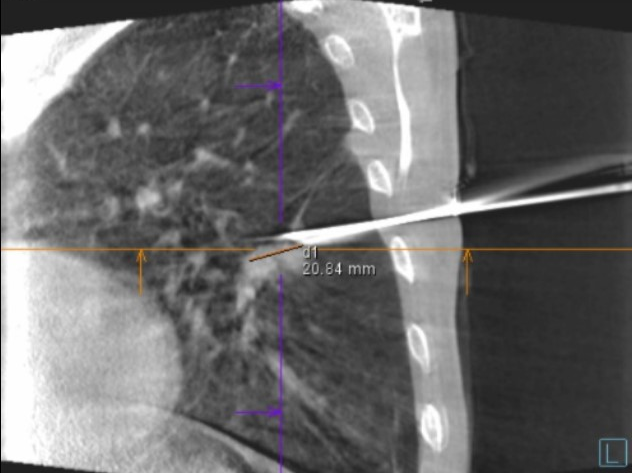

医生在CBCT引导下将消融治疗针经皮穿刺置入肿瘤病灶,在CBCT确定位置合适后连接至压缩氩气及氦气进行消融治疗。

术中针尖周围的冰球显示清晰,在CT下全程可视,可实现对肿瘤消杀精准,有效保护正常组织。